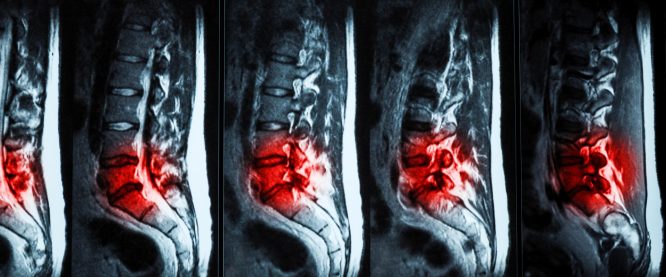

Πότε πρέπει να κάνω Μαγνητική Τομογραφία για τον πόνο στη μέση μου;

Η μαγνητική τομογραφία (ΜRΙ) της σπονδυλικής στήλης είναι μια πολύ χρήσιμη εξέταση, η οποία χωρίς ο ασθενής να δεχτεί ακτινοβολία, ...